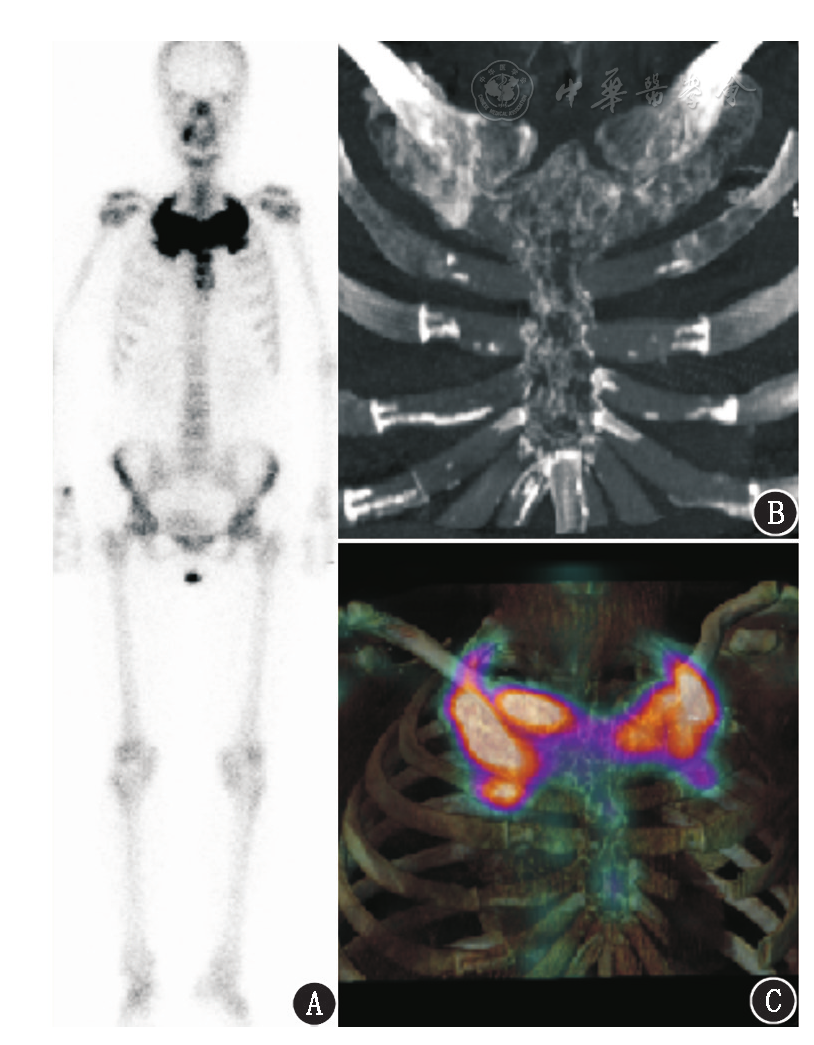

图1 乳腺癌根治术后骨转移患者(女,47岁)治疗前骨显像图.a.